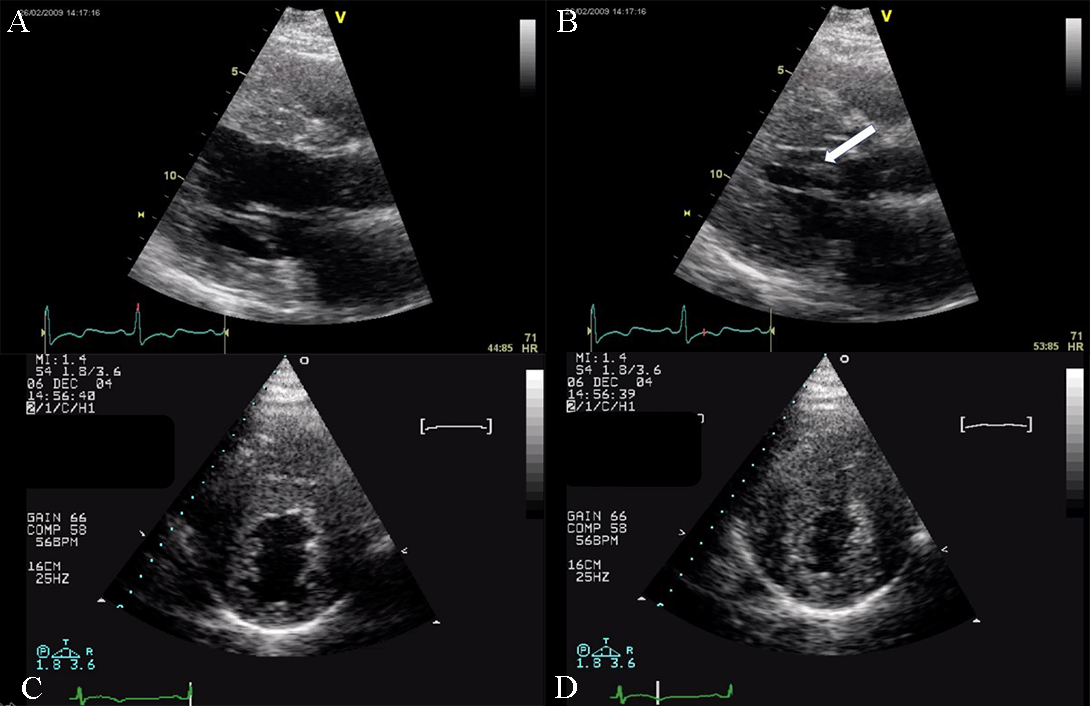

Fig. 5.Echocardiographic aspect of HCM. (A) Parasternal long-axis view diastolic frame showing increased thickness of septum and inferolateral wall. (B) Parasternal long-axis view systolic frame showing (arrow) systolic anterior motion of the anterior mitral valve. (C) Short axis view diastolic frame showing significant left ventricular hypertrophy. (D) Short axis view systolic frame showing reduced left ventricular end-systolic diameter.

Fig. 4.Echocardiographic aspect of HCM. (A) Apical 4 chamber view systolic frame, showing increased septum thickness. (B) Apical 4 chamber view diastolic frame. (C) Parasternal long-axis view- evidence of systolic anterior motion of the mitral valve. An online video of this patient with HCM is available (Appendix Video 4).